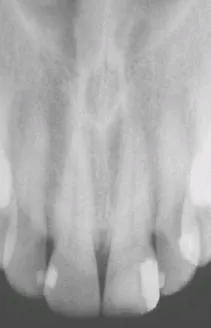

• 病灶位於硬腭中線 呈對稱外觀

• 位於腭乳頭(palatine papilla)後方

• 放射線 呈卵圓或圓形

• 不與失活性牙(nonvital tooth)密切相關

• 不與 門齒管(incisive canal)相通